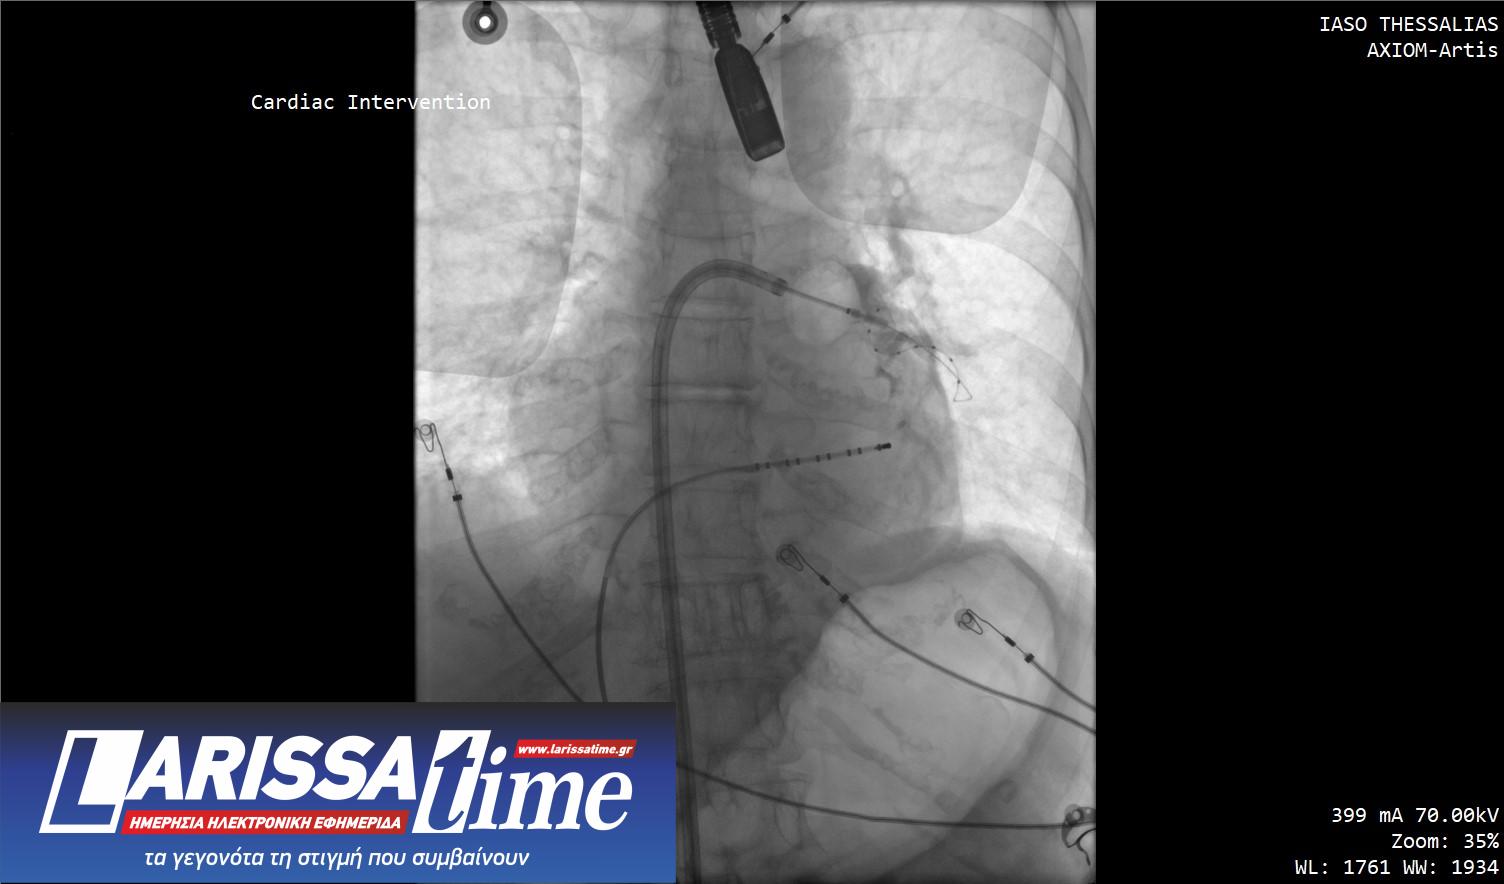

Στις συγκεκριμένες επεμβάσεις εφαρμόστηκε η σύγχρονη τεχνική κρυοκατάλυσης με τη χρήση ειδικού μπαλονιού κρυοπηξίας (Cryoballoon), το οποίο επιτρέπει την ελεγχόμενη ψύξη («πάγωμα») του καρδιακού ιστού γύρω από τις πνευμονικές φλέβες, επιτυγχάνοντας με ασφάλεια και ακρίβεια την ηλεκτρική τους απομόνωση. Η μέθοδος χαρακτηρίζεται από υψηλά ποσοστά επιτυχίας, μειωμένο χρόνο επέμβασης και ταχεία ανάρρωση των ασθενών.